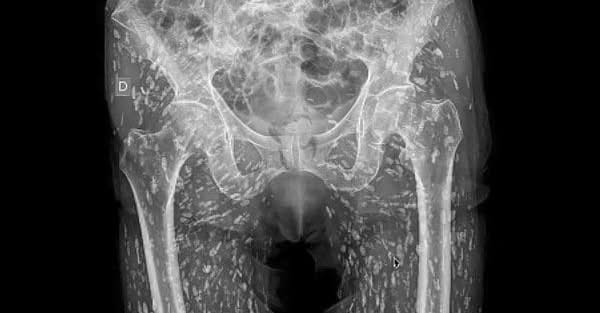

Il caso risale al 2021 ed è stato oggetto di studio da parte di un team di ricercatori presso l’ospedale universitario di Sao Joao a Porto. Durante la radiografia, sono state rilevate delle anomalie nel corpo del paziente, che si è recato in ospedale a causa di una caduta. L’immagine diffusa da Ghali sui social media mostra centinaia di noduli simili a “chicchi di riso”, che si sono rivelati essere cisti generate da un’infezione parassitaria. Il dottore ha definito questa radiografia come una delle “radiografie più folli” mai viste.

Il paziente, la cui identità è rimasta anonima, ha contratto questa condizione dopo aver ingerito carne di maiale poco cotta, contenente larve di tenia. Le larve penetrano nei tessuti corporei, formando cisti che, nel tempo, possono deteriorarsi e provocare infezioni, come la cisticercosi. Questa malattia parassitaria è causata dalla Taenia solium, comunemente nota come verme solitario, e può colpire vari organi del corpo umano, dai muscoli alla pelle, fino agli occhi e al sistema nervoso centrale. L’infezione si sviluppa quando l’uomo ingerisce le uova del parassita, frequentemente presenti nella carne di maiale poco cotta.

Il dottor Ghali ha chiarito che, incredibilmente, il paziente non era a conoscenza della sua condizione. “Queste cisti possono viaggiare ovunque in tutto il corpo. In questo paziente, hanno viaggiato pesantemente nei tessuti molli dei fianchi e delle gambe,” ha spiegato. La prognosi per la cisticercosi è generalmente buona, ma ci sono casi in cui l’infezione può risultare fatale. Si stima che circa 50 milioni di persone in tutto il mondo vengano infettate ogni anno da questa malattia, con circa 50.000 decessi.